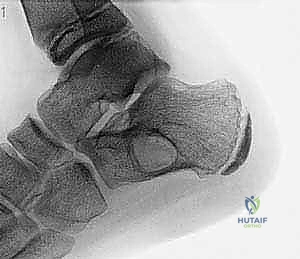

* التكوين النسيجي: لا يحتوي على سائل صافٍ، بل يحتوي على مساحات كيسية متعددة مملوءة بالدم. من الناحية المجهرية، هذه المساحات ليست أوعية دموية حقيقية (تفتقر للبطانة الوعائية)، بل تفصلها حواجز ليفية تحتوي على خلايا عملاقة (Giant Cells) وعظم غير ناضج. هذا التمييز النسيجي حاسم لفهم سبب نزيفها الشديد أثناء الجراحة وطبيعتها العدوانية.

صورة مجهرية توضح الفحص النسيجي لكيس العظم المتمدد (ABC)، حيث تظهر الحواجز الليفية والخلايا العملاقة التي تحيط بالمساحات المليئة بالدم، وهو ما يفسر السلوك العدواني الموضعي لهذا النوع من الأكياس.